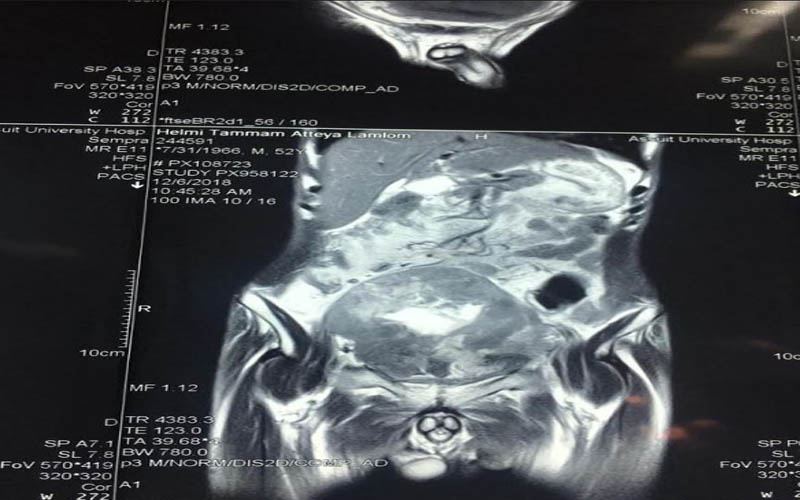

وعن تفاصيل العملية فقد أوضح الدكتور ضياء عبد الحميد الأستاذ بقسم جراحة المسالك البولية والكلى ورئيس وحدة أورام المسالك وقائد الفريق الطبي المسئول عن العملية ، أن تلك العملية تعد من أخطر عمليات استئصال أورام المثانة البولية وذلك نظراً لكبر حجم الورم واختراقه للأمعاء والأنسجة المجاورة من الشرايين والعضلات ، مما يشكل خطورة بالغة على حياه المريض والذي تم تعرضه لظروف معينة تسببت في إهماله للمرض لعدة سنوات ، مشيراً أن ذلك تم من خلال التنسيق والتعاون مع أعضاء قسم الجراحة العامة .

كما كشف الدكتور عمرو أبو فدان المدرس بقسم جراحة المسالك وعضو الفريق الطبي المسئول عن العملية انه فور وصول المريض إلى المستشفى تم خضوعه لعدد من الإشاعات والفحوصات الأولية والتي بينت تضخم حجم الورم مما يستلزم التدخل الجراحي لفصل الورم عن الأنسجة المحيطة وإنقاذ حياه المريض وبالفعل تم إجراء الجراحة بنجاح وخرج المريض من غرفة العمليات دون أي مضاعفات كما تم متابعة الحالة فى غرفة العناية المركزة لمدة 24 ساعة وعند استقرار حالة المريض تم نقله إلى غرفته بمستشفى جراحة المسالك البولية والكلى ، وفى السياق ذاته نوه أن نجاح العملية تم بفضل تضافر جهود الفريق الطبي بقسم جراحة المسالك البولية والكلى وعلى رأسه الدكتور حسنى البهنساوى الأستاذ المساعد بالقسم ، ومدرسين القسم وهم الدكتور أيمن عاصم ، و محمد أسامه ، وعمرو عصام ، والمعيد محمد عماد الدين ، إلى جانب فريق التخدير بقيادة الدكتور محمد أنور المدرس بقسم التخدير والعناية المركزة .